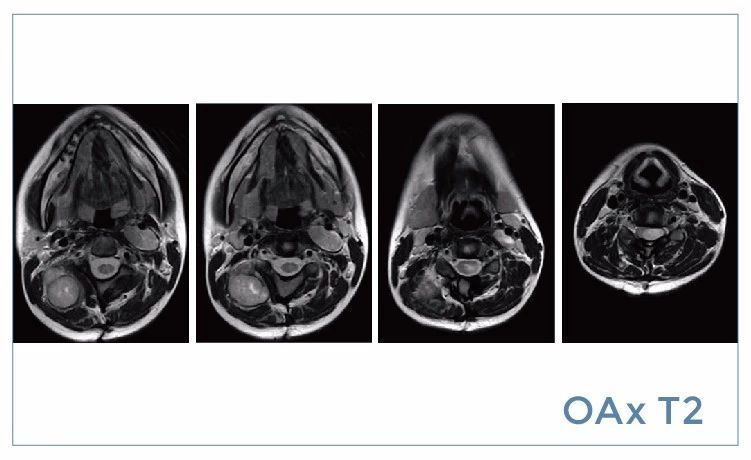

【朗润影像档案】磁共振影像病例分享(编号20190816)